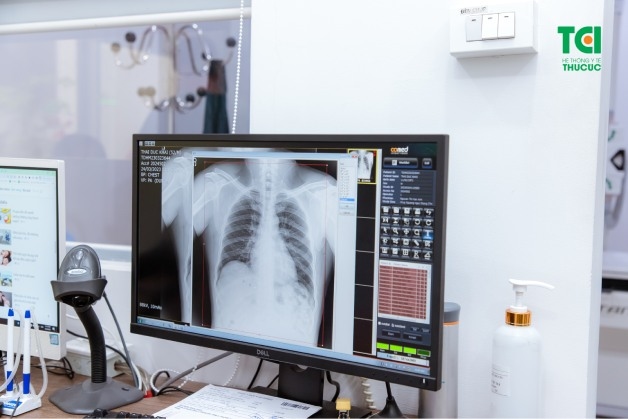

Chụp X quang phổi là phương pháp thường gặp trong quá trình sàng lọc các bệnh lý liên quan tới phổi. Với kỹ thuật này, người bệnh sẽ được hướng dẫn đứng trước tấm chứa phim X quang hoặc một đầu thu đặc biệt để ghi lại hình ảnh của tim, phổi, đường thở, mạch máu và hạch bạch huyết.

Chụp X quang là phương pháp chỉ định thường gặp trong quá trình sàng lọc các bệnh lý liên quan tới phổi

Máy chụp X quang sẽ chiếu tia X vào người bệnh, tia X sẽ xuyên qua các cơ quan của lồng ngực và thu lại hình ảnh của tim, phổi, xương lồng ngực… Dựa vào kết quả hình ảnh, bác sĩ có thể xác định và chẩn đoán sớm một số bệnh lý như: